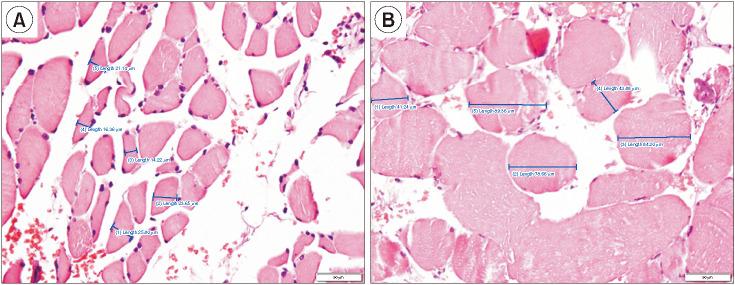

This study used a case-control design with 23 patients in the case group (patients unable to walk independently) and 23 patients in the control group (patients able to walk independently). Sampling was carried out consecutively according to the inclusion and exclusion criteria based on the medical records of patients with hip fractures after bipolar hemiarthroplasty at our hospital. In the preoperative period, hand grip strength (HGS), mid-upper arm muscle area (MUAMA), calf circumference (CC), serum albumin level, and total lymphocyte count were measured. A muscle biopsy was performed intraoperatively from the gluteus muscle with the amount of 200-350 mg. The patient's walking ability was assessed in the polyclinic using the Timed Up and Go test 6 weeks postoperatively. The statistical tests used were descriptive statistics, proportion comparison analysis with the chi-square test, and multiple logistic regression test.

Univariate analysis using chi-square test proved HGS, MUAMA, CC, serum albumin level, and muscle fiber diameter as risk factors for inability to walk independently 6 weeks after bipolar hemiarthroplasty ( = 0.003, = 0.003, = 0.006, = 0.044, and = 0.000, respectively). Logistic regression test proved 3 direct risk factors for the inability to walk independently 6 weeks after bipolar hemiarthroplasty, namely MUAMA, serum albumin level, and muscle fiber diameter, as the strongest predictive factor (adjusted odds ratio, 63.12).

Low MUAMA, serum albumin levels, and muscle fiber diameter are direct risk factors for the inability to walk independently in hip fracture patients 6 weeks after bipolar hemiarthroplasty.